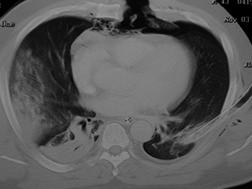

Contuzie pulmonara stanga Contuzie pulmonara dreapta

Contuzie pulmonara dreapta.Imagine CT